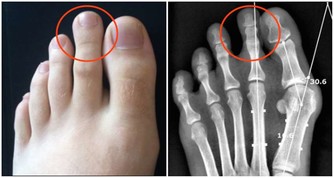

三、隱匿性抑鬱症情緒低下和憂鬱症狀並不明顯,常常表現為各種軀體不適症狀,如心悸、胸悶、中上腹不適、氣短、出汗、消瘦、失眠等。